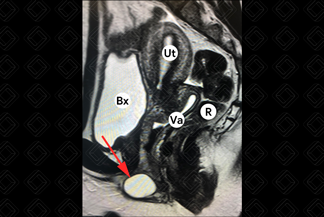

Texto alternativo para a imagem Figuras 1 e 2. Créditos: Dra. Elazir Mota - Rio de Janeiro/RJ

Descrição das figuras 1 e 2: Ressonância magnética da pelve; planos axial e sagital. Presença de cisto de glândula de Bartholin no introito vaginal esquerdo (setas vermelhas). Bx = bexiga, Ut = útero, Va = vagina, R = reto.

Exames de imagem: Na maioria dos casos, são identificados na ressonância magnética da pelve como lesão ovalada ou arredondada, com dimensões que variam de 3 a 5 cm, com sinal hiperintenso em T2 e hipointenso em T1, com discreta ou ausente captação parietal do meio de contraste. Diante de quadros infecciosos ou sangramento, pode haver hipersinal em T1 (figuras acima). Nos casos de cistos volumosos ou que crescem por alguma complicação, como abscesso, eles podem ser observados na tomografia computadorizada da pelve.